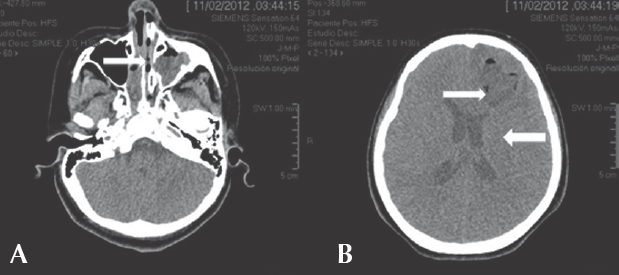

Tres días después, presentó bradicardia, hipertensión y deterioro de la escala de Glasgow a 10 puntos. Requirió ventilación mecánica y terapia intensiva. Se realizó nueva tomografía de cráneo (Figura 2) que mostró empiema interhemisférico inoperable causado por pansinusitis complicada y edema cerebral secundario. Se agregó metro-nidazol al tratamiento.

Figura 2 A) Pansinusitis (flecha). B) Imagen frontal derecha polar heterogénea sin reforzamiento en la periferia (flecha delgada) e imagen nueva hipodensa interhemisférica derecha homogénea de 0.4 cm de grosor, aunque sin efecto de volumen (flecha gruesa).